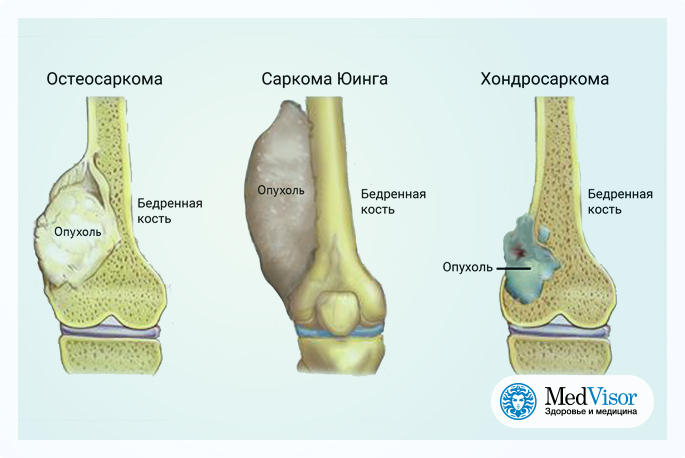

Остеосаркома коленного сустава: информация и поддержка